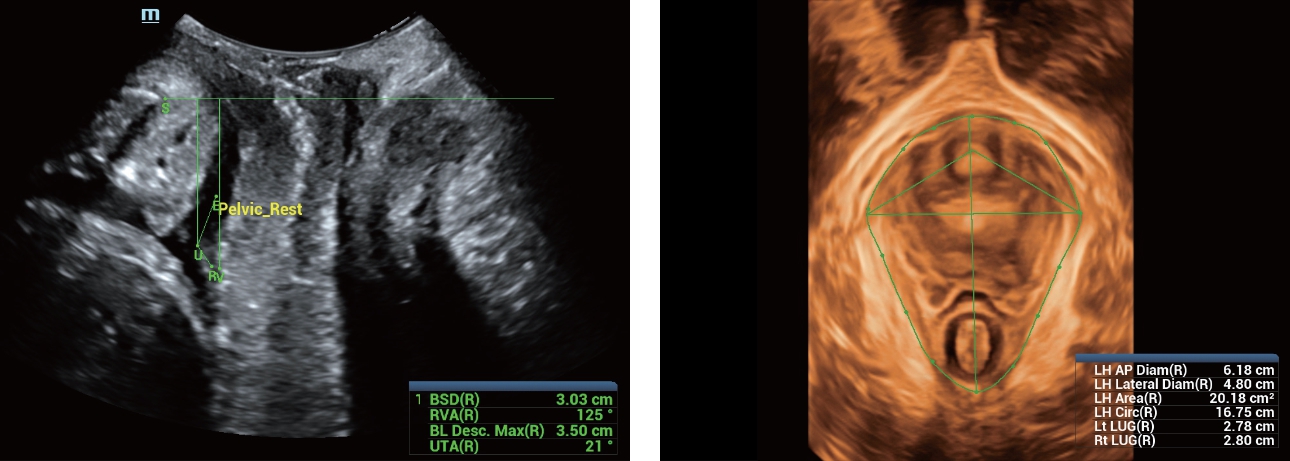

Naast de hoogwaardige beeldvormingskwaliteit verbetert de Resona 7 tevens de klinische onderzoeksmogelijkheden met de revolutionaire V Flow voor vasculaire hemodynamische evaluatie, en de intelligentste vlakacquisitie van een 3D-gegevenssets voor de diagnose van het foetale, centrale zenuwstelsel. Met zijn combinatie van de meest intu?tieve, op vingerbewegingen gebaseerde multi-aanrakingsbediening en alle essenti?le klinische functies loopt de Resona 7 voorop in de nieuwe golven van ultrasoundinnovatie.